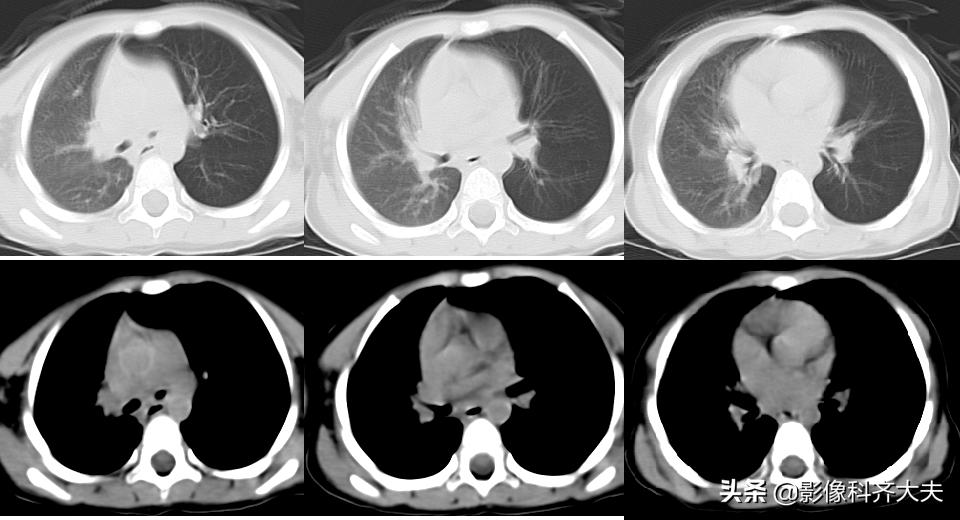

病例3、病史:患儿,两岁半。咳嗽近一个月,外院按支气管炎治疗半个月无好转。询问家属是否有吃东西呛咳病史,家属回忆一个月前还在好像吃过花生,瓜子,但不能完全确定。

图像显示在气管分叉的位置有一“瓜子”形异物的存在,尤其是冠状位显示更明显。

病例4、病史:患者男、13岁,误食“钉子

轴位图

冠状位图

通过以上病例可见:CT的MPR冠状位,可直接发现异物的位置,形状和大小,以及邻近组织区域变化。